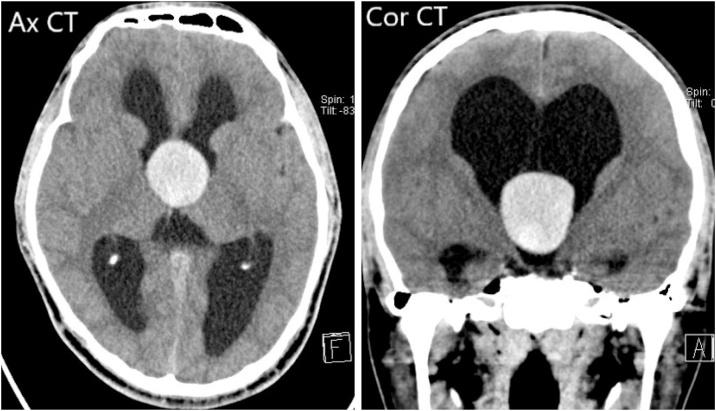

Colloid cysts are benign cystic lesions located at the anterior part of the third ventricle mostly at the foramen of Monro and contain colloid material. Hemorrhage in a colloid cyst is exceedingly rare. Only 15 clinically diagnosed cases of haemorrhagic cysts were reported in the literature and 5 more cases on autopsy. Here we report two rare cases of a haemorrhagic colloid cyst describing the atypical radiological findings, the undertaken surgical procedures and histopathological results.

We presented 2 cases of haemorrhagic third ventricle colloid cysts. First case is a 27-year-old male patient, presented with dizziness, nausea, vomiting and blurring of vision. He was operated by transcortical endoscopic transventricular excision of a third ventricular cyst and the insertion of external ventricular drain. The second patient is a 21-year-old male, presented with history of worsening headache for 1 month associated with blurring of vision. The patient had a transcortical microscopic, transventricular cyst excision.

胶样囊肿是位于第三脑室前部的良性囊性病变,大多位于孟氏孔,内含胶样物质。胶样囊肿出血极为罕见。文献中仅报道了15例临床诊断的出血性囊肿病例,尸检中又发现5例。在此,我们报告两例罕见的出血性胶样囊肿病例,描述其非典型影像学表现、所采取的手术方式及组织病理学结果。

我们展示了2例第三脑室出血性胶样囊肿病例。第一例是一名27岁男性患者,表现为头晕、恶心、呕吐及视力模糊。他接受了经皮质内镜经脑室第三脑室囊肿切除术及外置脑室引流管置入术。第二例患者是一名21岁男性,有1个月头痛加重病史,伴有视力模糊。该患者接受了经皮质显微镜下经脑室囊肿切除术。